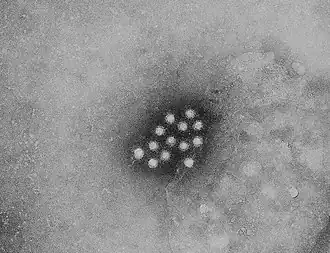

Virale

Les hépatites virales sont les hépatites A, B, C, D, E et G. Une hépatite F pourrait exister, mais les recherches n'ont pas abouti à l'heure actuelle.

Les cinq virus principaux sont l'hépatite A et E (causées par l’ingestion d’eau ou d’aliments contaminés) et l'hépatite B, C et D (habituellement survenant après un contact parentéral avec des liquides biologiques contaminés)[3]. L’hépatite B peut se transmettre par voie sexuelle.